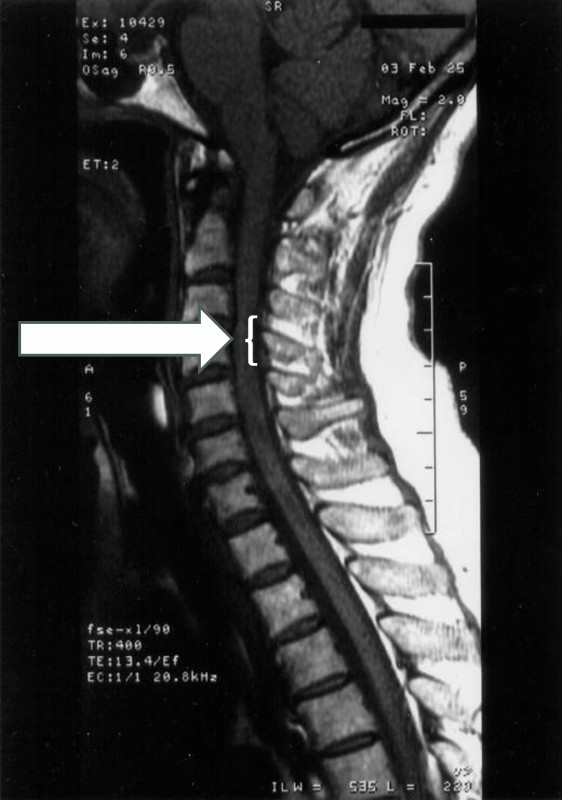

この結果再度画像診断が行なわれ、①C3・C4レベルの頸椎の変形(図3)、および②右側椎骨動脈の低形成とが指摘された。図4は、脳外科の回答後にわれわれが立ち合って撮影しなおしたMRAで、図5に模式図として示したように右側椎骨動脈の低形成が認められる。

図3